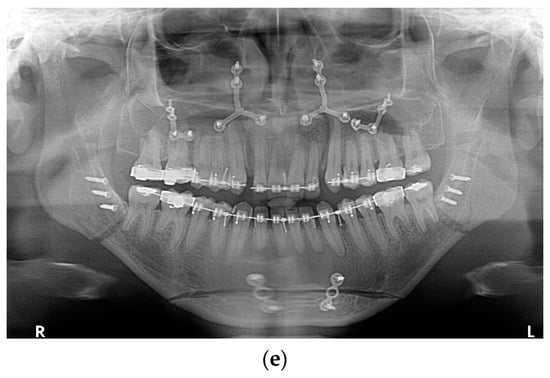

All fixation hardware used in orthognathic procedures was made of titanium (Figure 1).

Figure 1.

Panoramic X-ray with fixation hardware: (a) after BSSO; (b) after BSSO and genioplasty; (c) after Le Fort I osteotomy; (d) after bimax; (e) after bimax with maxillary segmentation and genioplasty.